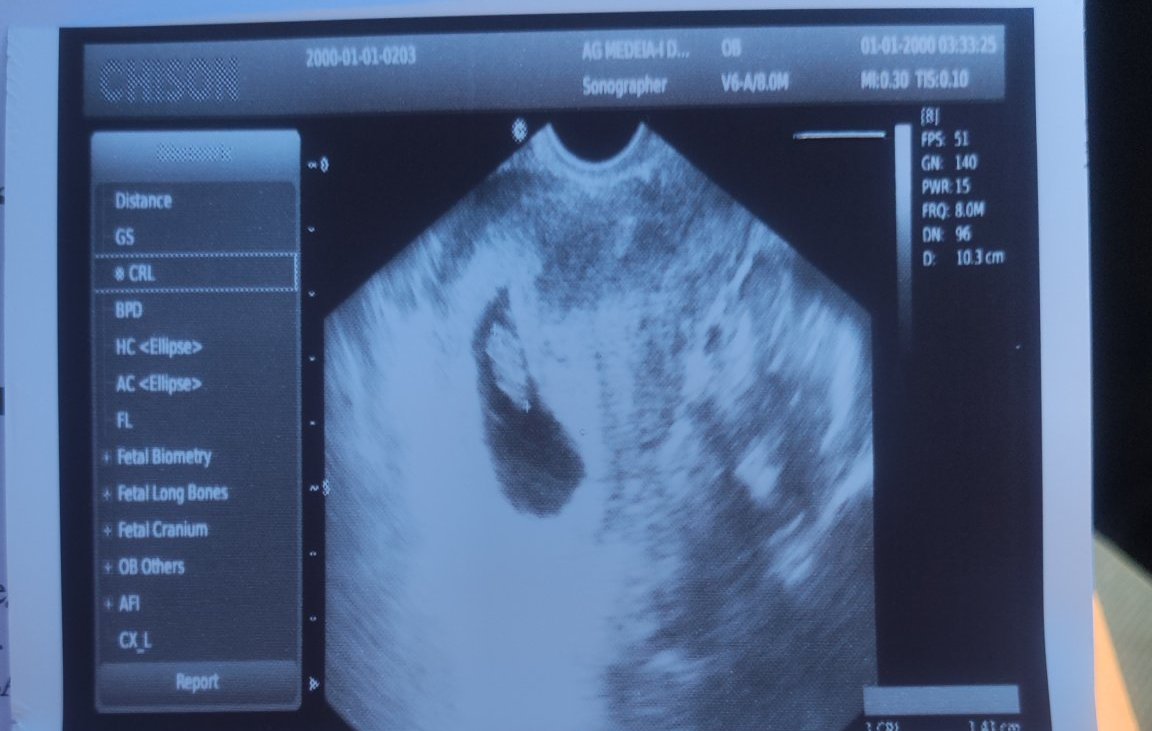

Здравейте, моля за отговор, понеже бях си пуснала въпроса в друга тема и там не получих такъв. Бременна съм в 8 г.с. +3 дни и онзи ден точно в 8г.с. бях на преглед и видяхме бебо + сърдечна дейност, но някак си на снимката ми изглежда нестандартно или някак много неоформено. Не знам дали е от самата апаратура или нещо друго , но съм била бременна и преди и точно в тази седмица бебчето си се виждаше много по-добре и оформено.. Прикачвам снимка

• Мнения: 1 107

АГ не е направил добра снимка според мен. Наистина изглежда безформено, но според мен е от ъгъла, който е поставен ехографа. Предполагам, че с вагинален са те гледали.

Iliyanaah,не изглежда да има някакъв проблем. Да, сакът не е идеално симетричен, но сам по себе си не е проблем.

• Мнения: 193

Да , момичета с вагинален ме гледаха, но при първата ми бременност бебчето в 8г.с. изглеждаше така даже беше с коремен ехограф

За това се чудя малко ...

Ако имаше проблем, АГ щеше да каже. Според мен лошо направена снимка. Всичко е наред. На бебето му трябва спокойна мама сега.